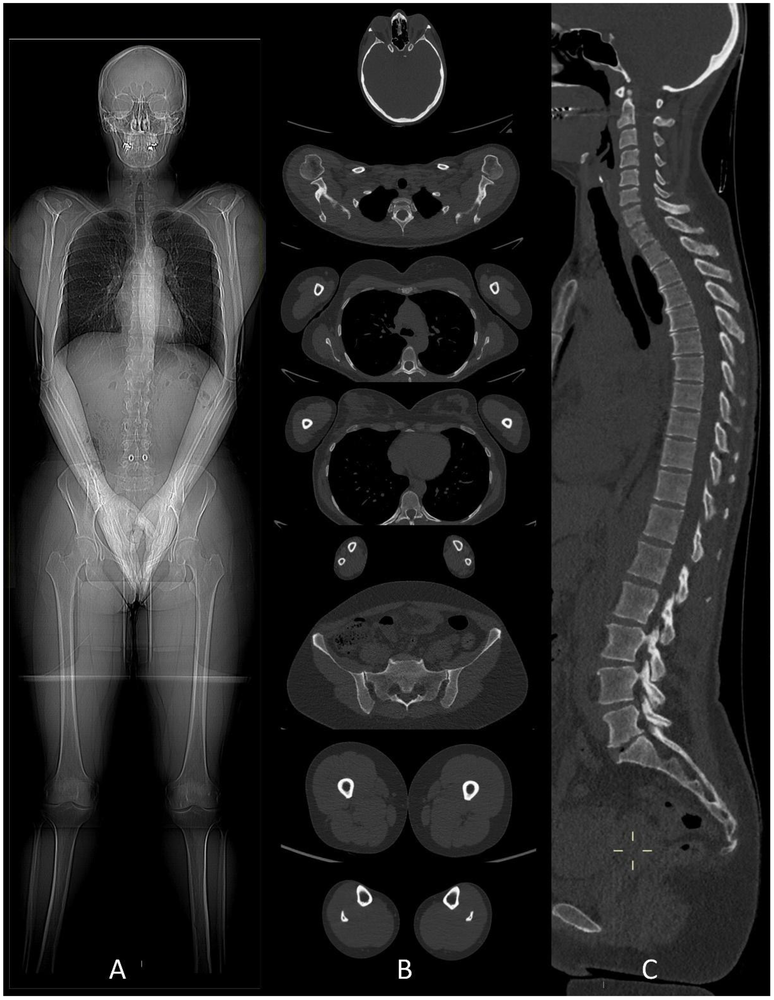

Figures ci-dessus : Accident de moto sur circuit, intubation sur place. Le body-scanner révèle un hématome sous dural supra-tentoriel gauche, de multiples petites contusions cérébrales hémorragiques, une fracture isolée du condyle occipital droit, une contusion du rein gauche avec lame d’hématome sous capsulaire.